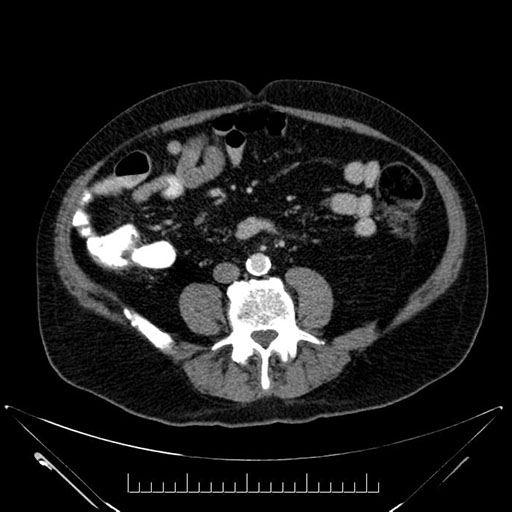

Axial - stented